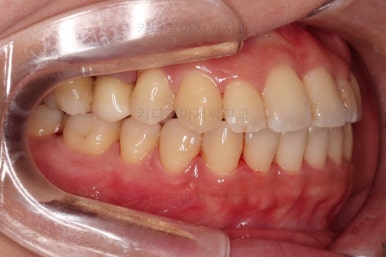

초진 시, 입안의 모습이에요.

결손부위가 눈에 띄고요.

결손부위가 양쪽에 있다보니 윗니 중간에 틈새가 벌어졌네요.

뒤쪽의 빈공간으로 치아들이 도미노처럼 쓰러져서 그렇습니다.

앞니의 약간의 틈새, 약간의 삐뚤어짐, 약간의 중앙선 틀어짐 등 심하진 않으나 약간씩의 문제점들이 있네요.

임플란트 보철이 깔끔하게 들어갔고, 교정치료도 마무리가 되었습니다.

부산연산동치과 전후 사진을 비교해 보겠습니다.

총 22개월 걸렸고, 임플란트는 1개로 마무리를 했습니다.